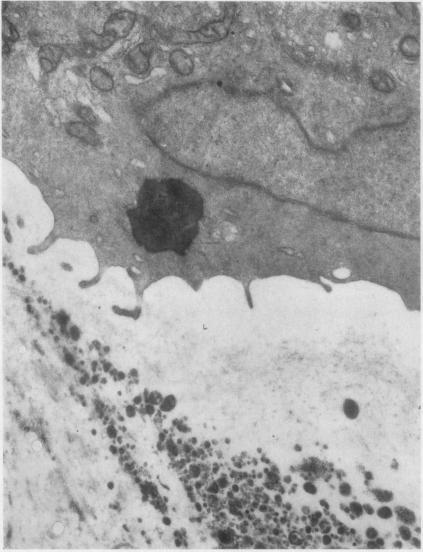

EXTRA-CELLULAR LIPID IN THE MATRIX OF HUMAN ARTICULAR CARTILAGE.

Ann Rheum Dis. 1965 Mar;24(2):136-46. doi: 10.1136/ard.24.2.136.